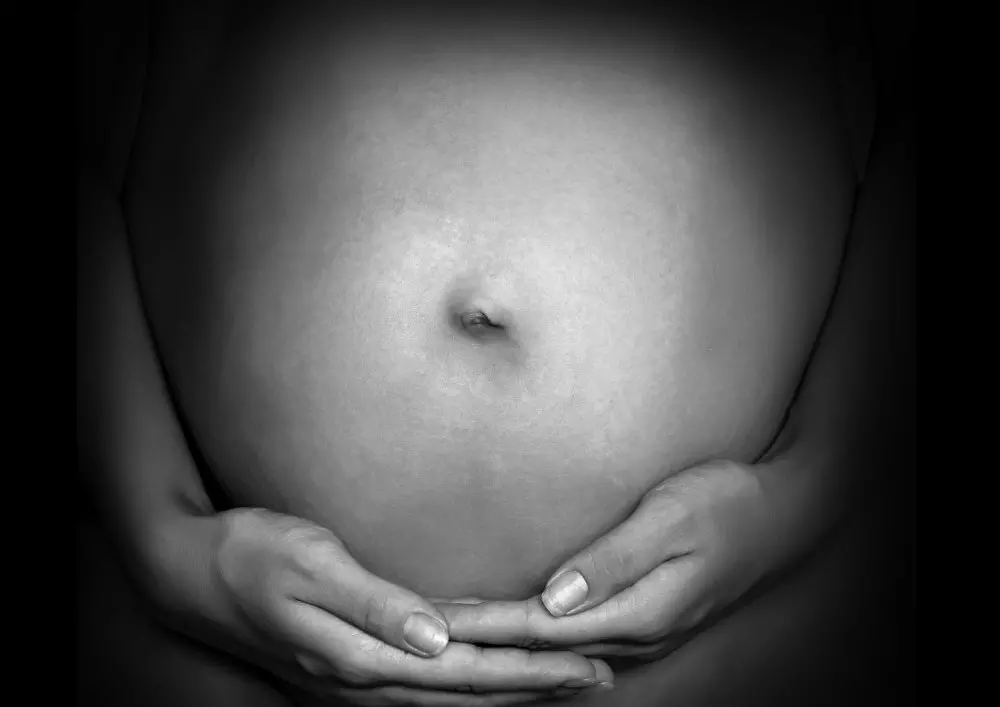

Kinesiology tape w dysfunkcji spojenia łonowego w ciąży

W dziale „Nowoczesne metody fizjoterapii” znajdą Państwo artykuł, w którym prezentujemy zastosowanie kinesiology tape w przypadku dysfunkcji spojenia łonowego u kobiet w ciąży. Problem ten powoduje poważne dolegliwości bólowe, a przyjmowanie leków przeciwbólowych w okresie ciąży nie jest zalecane. Coraz częściej ciężarne kierują się w takiej sytuacji do fizjoterapeuty i choć kinezyterapia oraz fizykoterapia nie są najlepszą drogą do rozwiązania dolegliwości bólowych, bardzo dobrze i czasami niemal natychmiastowo działa technika kinesiology tape.